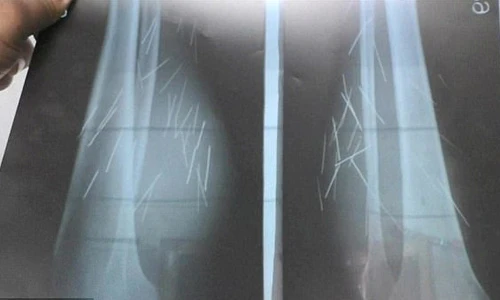

"Chúng tôi đã chụp X-quang toàn thân cho cô ấy và phát hiện 70 loại kim sắt khác nhau ở chân dưới đầu gối. Về mặt y khoa, không thể cho các cây kim như vậy phát triển trong cơ thể con người. Cho đến nay, chúng tôi chưa thể xác nhận làm thế nào mà kim châm vào cơ thể cô ấy nhưng chúng tôi nghi ngờ bệnh nhân đã tự làm hại mình”, bác sĩ Vishal chia sẻ. Ảnh: CAP.